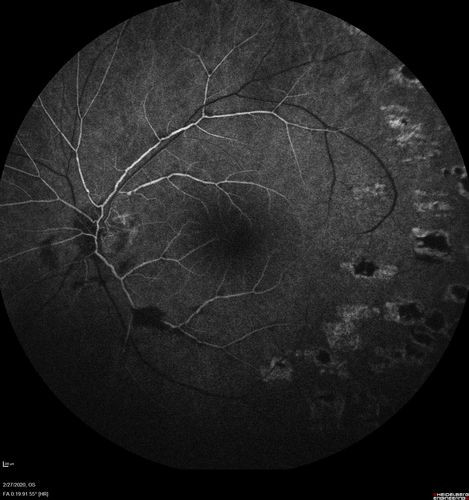

Eales Disease and fresh vitreous hemorrhage - 20 year old man

20 year old mane with fresh vitreous hemorrhage in the right eye.  At age 15 he had a PPV and laser in the left eye and laser in the right eye.  The vision is OD 20/80 PH 20/25, OS 20/25.  The left eye has a mild cataract.  He had prior testing for coagulopathies which was negative.  Testing done for syphillis and TB was negative.  Additional laser was done to prevent further bleeding in the right eye.